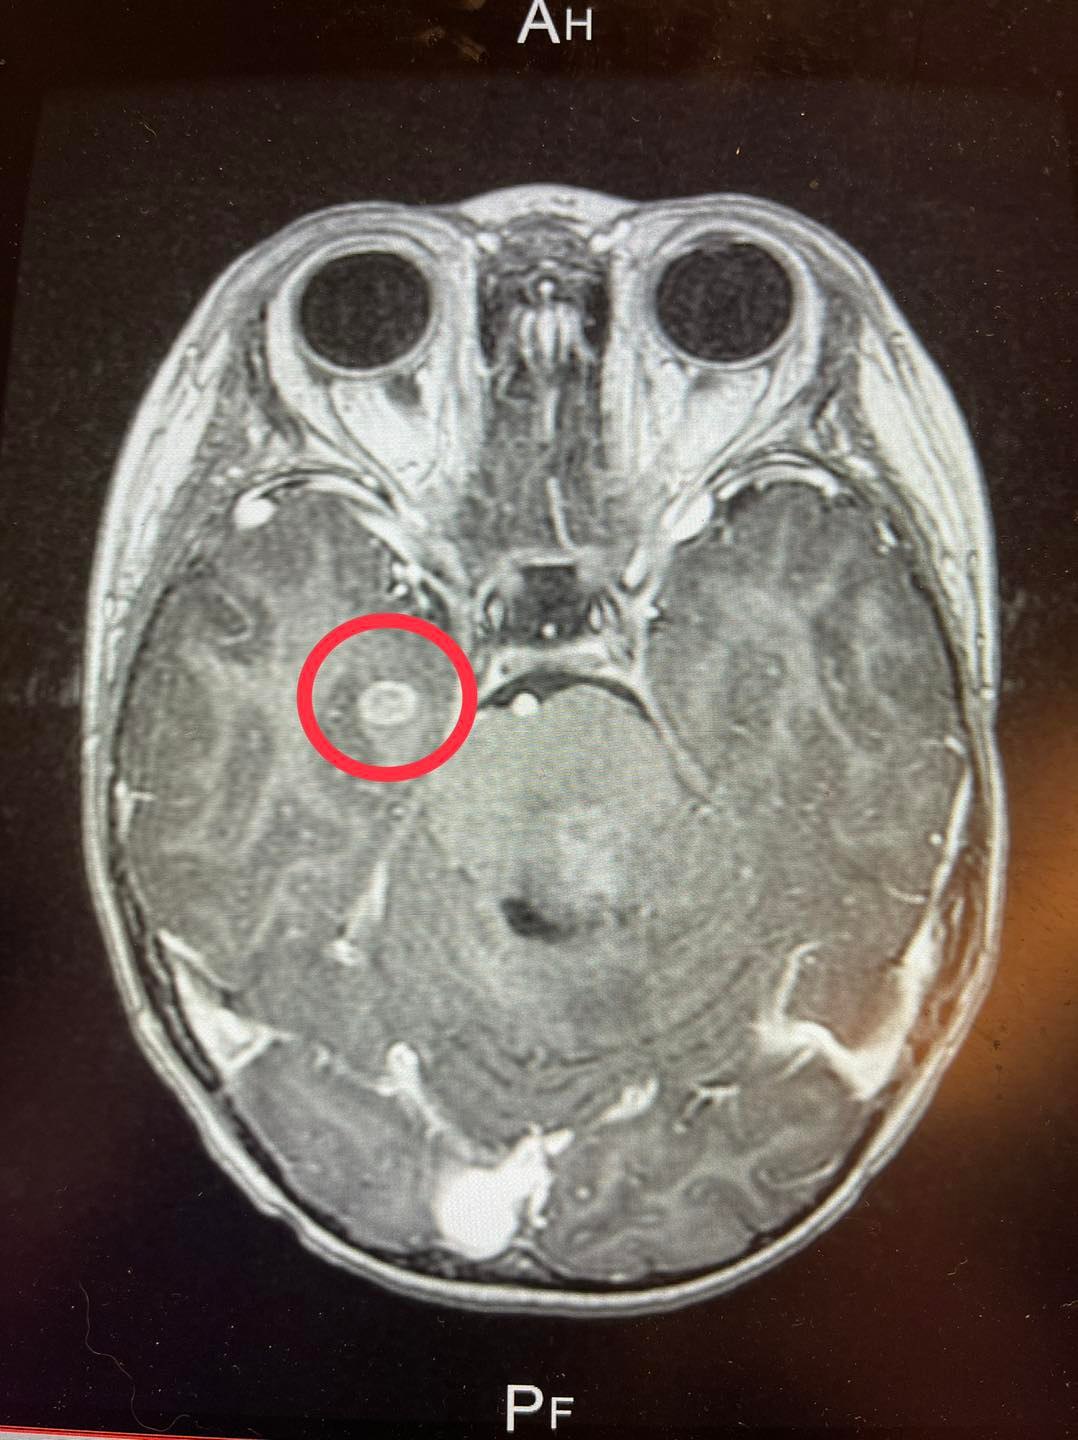

于1/12在小儿科医师的建议下要我们去大医院挂急诊,我们抱著忐忑不安的心情直冲荣总挂急诊,医生问诊之后马上安排晨去照CT影片上发现晨的脑干有个约6公分大小的阴影,疑似脑癌,当晚安排照MRI,住进加护病房。

•     1/13 MRI的影像分析结果确诊是弥漫性内生性脑干胶质瘤(DIPG)。

(晨翔的脑部分析。)